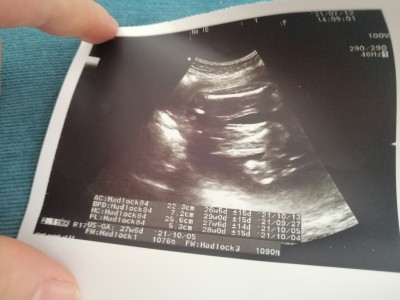

Arkadaşlar bugün doktora gittim hiç memnun kalmadım bi dakika bile sürmedi bakması hatasıyla uyumlu dedi bu ultrason kağıdını verdi boy kilo yazıyor mu burada ben anlayamadım

Gebelik haftası 27+3

Boyu 37.1 cm.

Kilosu 1076 gram.

Boyu FL ile yazan kısım. 7 ile çarpmak gerek tam boyunu hesaplamak için.

Canım 37cm 1kilo76grm bebişin :)

Fw yazan kilosu

Fl yazanı da 7 ile çarpınca boyu çıkıyor